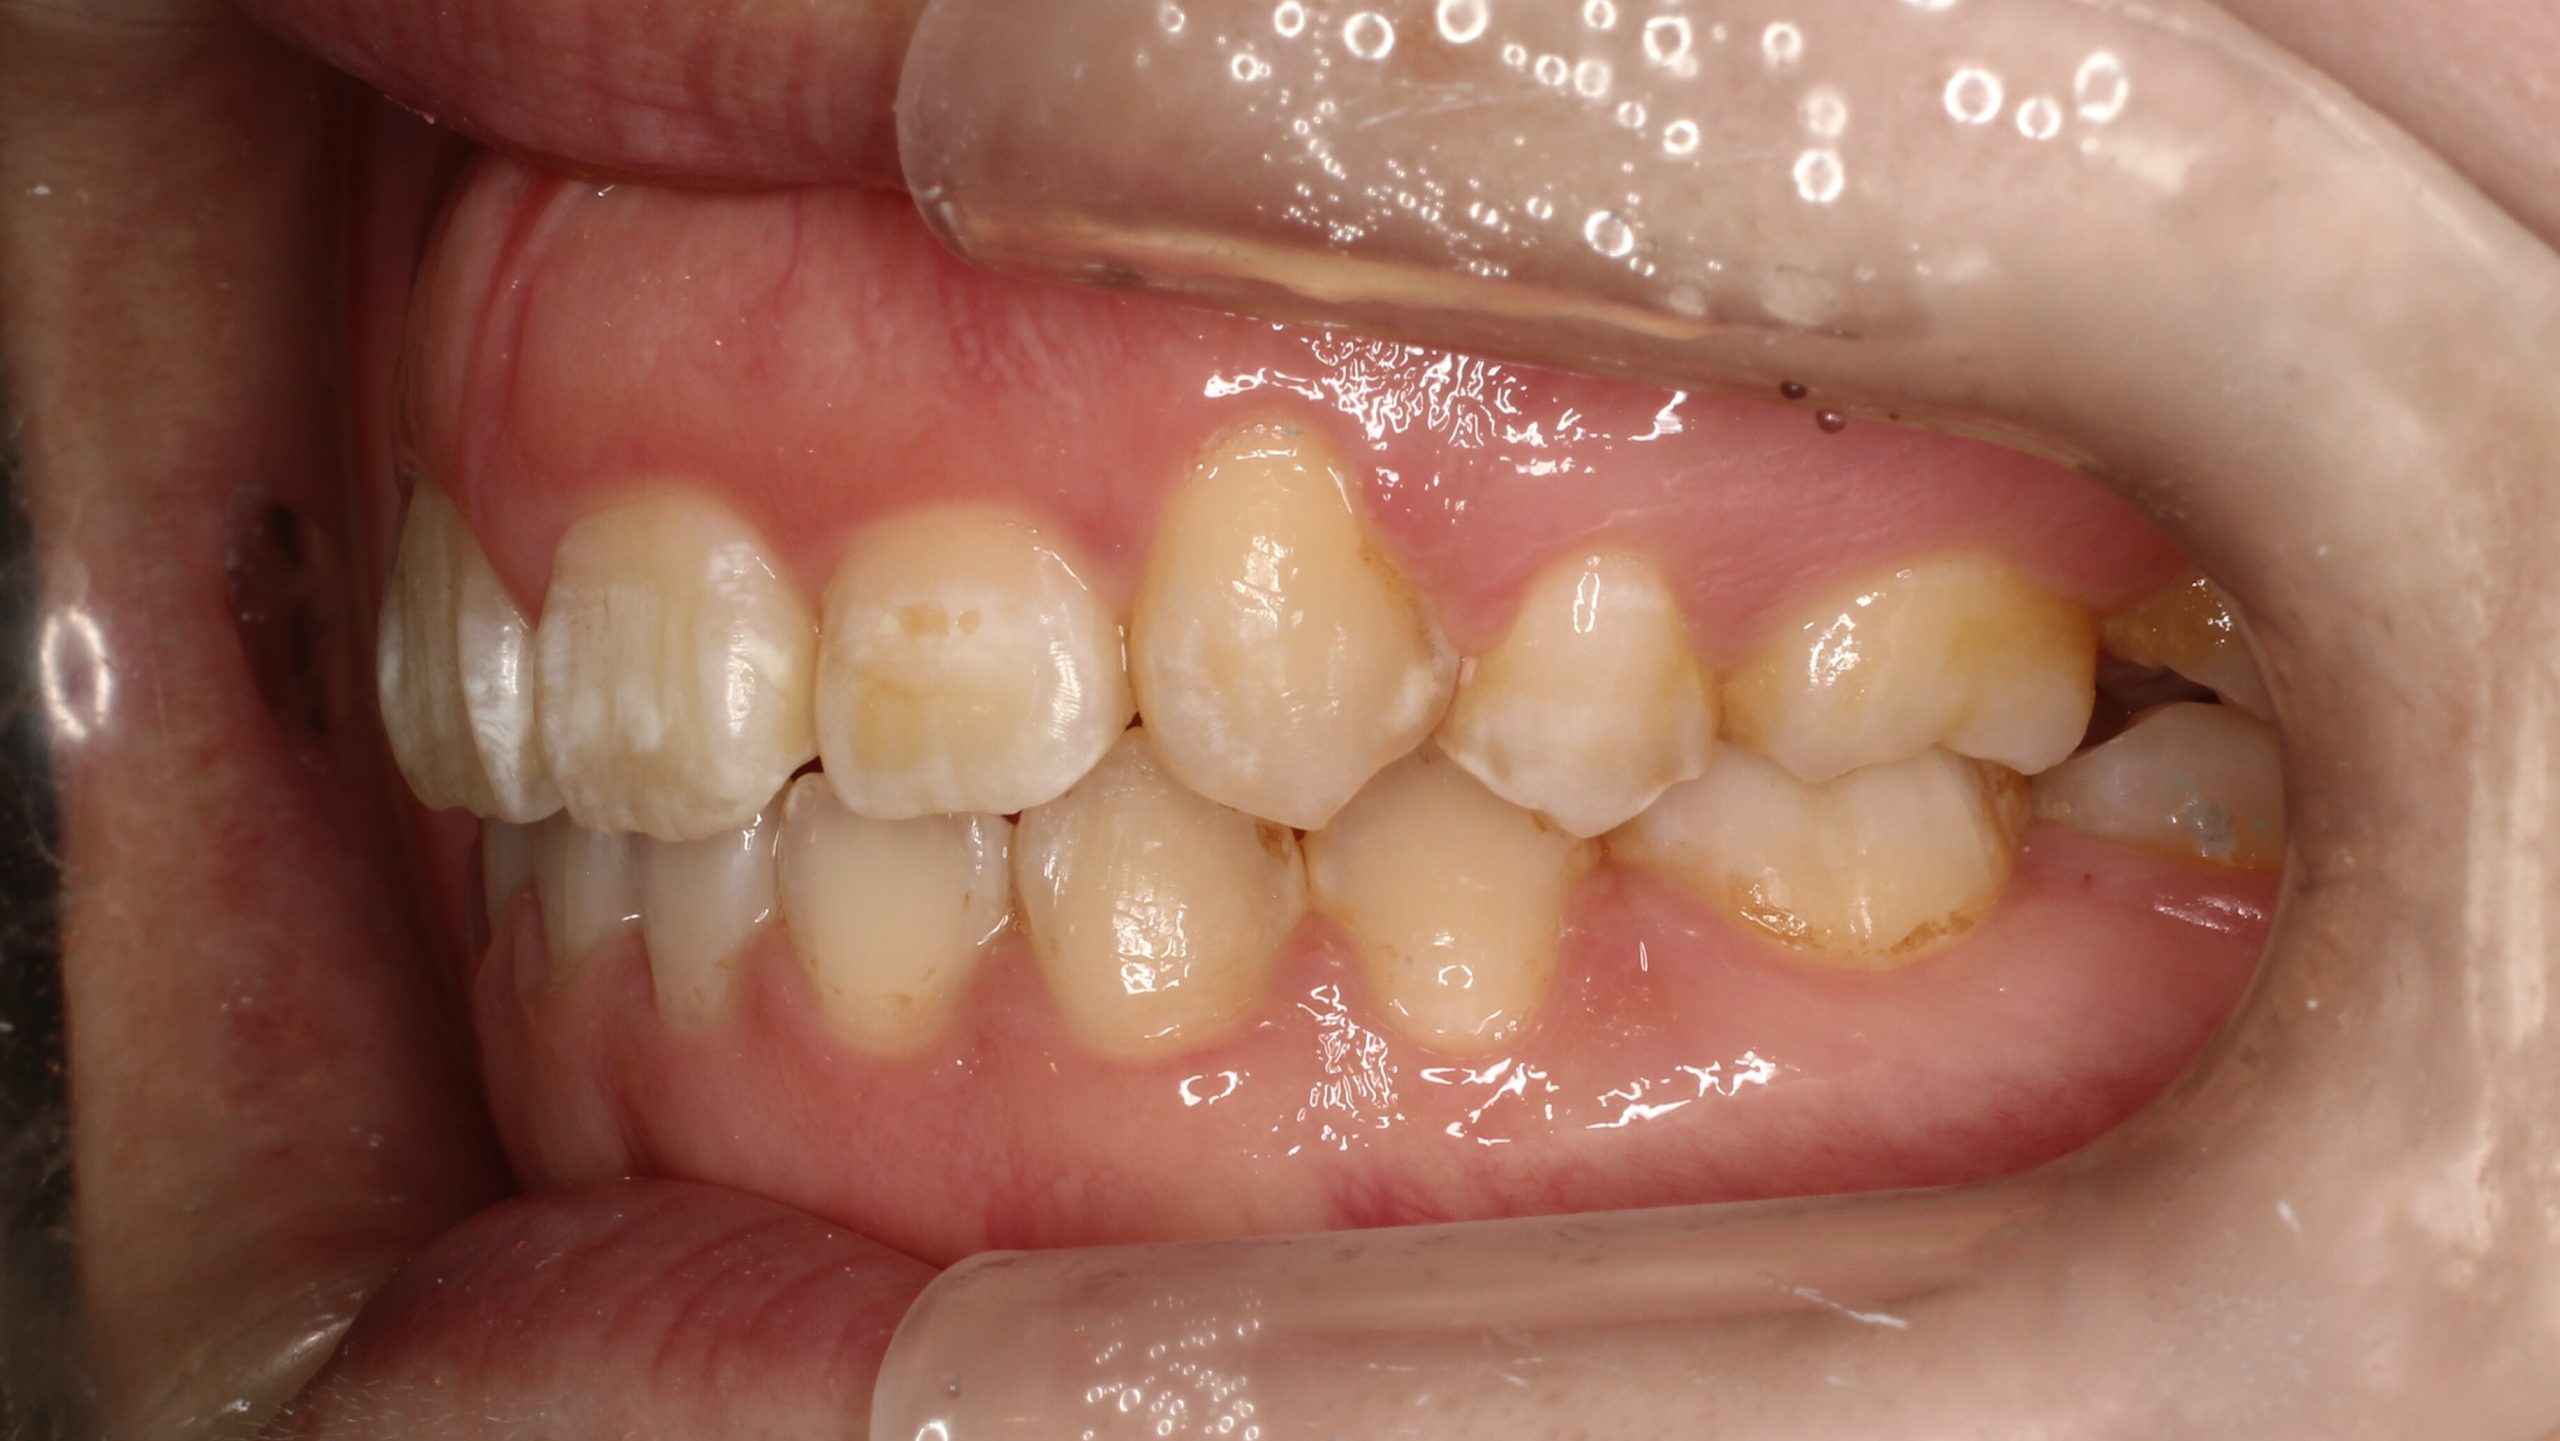

上の歯が出ている、嚙み合わせが悪い(治療期間:2年4か月/通院32回)

Before